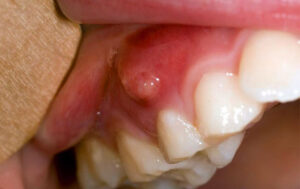

| Áp xe nha chu | Liên quan viêm nướu/viêm nha chu, túi nha chu sâu, cao răng; hay bị kích hoạt bởi kẹt thức ăn trong túi nha chu | Nướu sưng đỏ, đau khi chạm; có thể thấy mủ rỉ ra; cảm giác răng “cộm”/khó chịu vùng quanh răng |

- Nướu sưng, có điểm sưng như “mụn” hoặc chảy mủ.